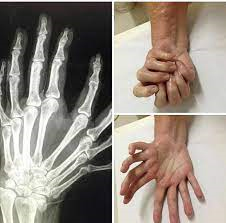

Ulnar dimelia or mirror hand syndrome is a rare congenital anomaly of the upper limb characterised by absence of the radial ray (including thumb), duplication of the ulna and duplication of the ulnar halves of the carpals, metacarpals and phalanges.

Al-Qattan and Al-Thunayan et al. have propesed a classification for mirror hand spectrum 5,6. The system divides the condition into five types as follows:

• type 1: there is ulnar dimelia showing two ulnae with absent radius

• type 2: an intermediate form having two ulnae and a radius

• type 3: also an intermediate form having mirror hand polydactyly with one radius and one ulna

• type 4: a syndromal mirror hand with fibular dimelia (Laurin Sandrow syndrome)

• type 5: multiple hands on the end of forearm